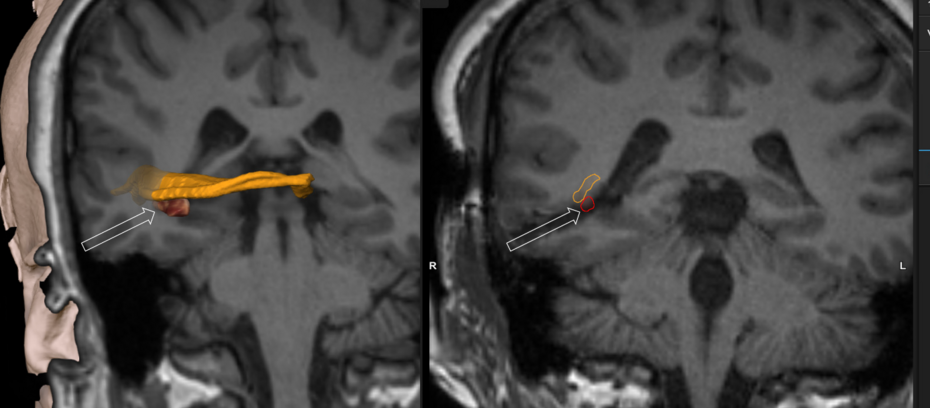

Durch Computertomographie (CT) und Kernspinresonanztomographie (MRT) kann eine Neoplasie im Gehirn effektiv nachgewiesen werden. Zur Identifizierung von Läsionen ist die MRT empfindlicher als die CT, weist aber für Patienten mit Herzschrittmachern, inkompatiblen Prothesen, Metallklammern und anderem Kontraindikationen auf. Die CT bleibt die Methode der Wahl, um Verkalkungen innerhalb der Läsionen oder Knochenerosionen der Schädeldecke oder -basis zu erkennen. Die Verwendung von Kontrastmitteln, die im Fall der CT jodiert und im Fall der MRT paramagnetisch (Gadolinium) sind, ermöglicht die Erfassung von Informationen über die Vaskularisation und Integrität der Blut-Hirn-Schranke, eine bessere Definition der Tumorgeschwulst im Vergleich zum umgebenden Ödem und die Erstellung von Hypothesen über den Grad der Malignität. Die radiologische Untersuchung ermöglicht auch eine Bewertung der mechanischen Auswirkungen und die daraus resultierenden Veränderungen der Gehirnstrukturen, die sich durch den Tumor ergeben, wie zum Beispiel Hydrocephalus und Hernien, deren Auswirkungen tödlich sein können. Schließlich kann mit dieser Diagnostik in Vorbereitung einer Operation der Ort der Läsion oder die Infiltration des Tumors in lebenswichtige Bereiche des Gehirns bestimmt werden. Zu diesem Zweck ist die MRT effizienter als die CT, da sie dreidimensionale Bilder liefern kann.

Bei Diagnose und Behandlung dieser Läsionen wurden in jüngster Zeit erhebliche Fortschritte erzielt, wodurch das Überleben und die Kontrolle der Symptomatik verbessert wurden. Das Auftreten von Anzeichen und Symptomen ähnelt denen anderer massiver Läsionen im Gehirn. Das Diagnoseverfahren der Wahl ist die Kernspintomographie unter Verwendung von Kontrastmitteln.